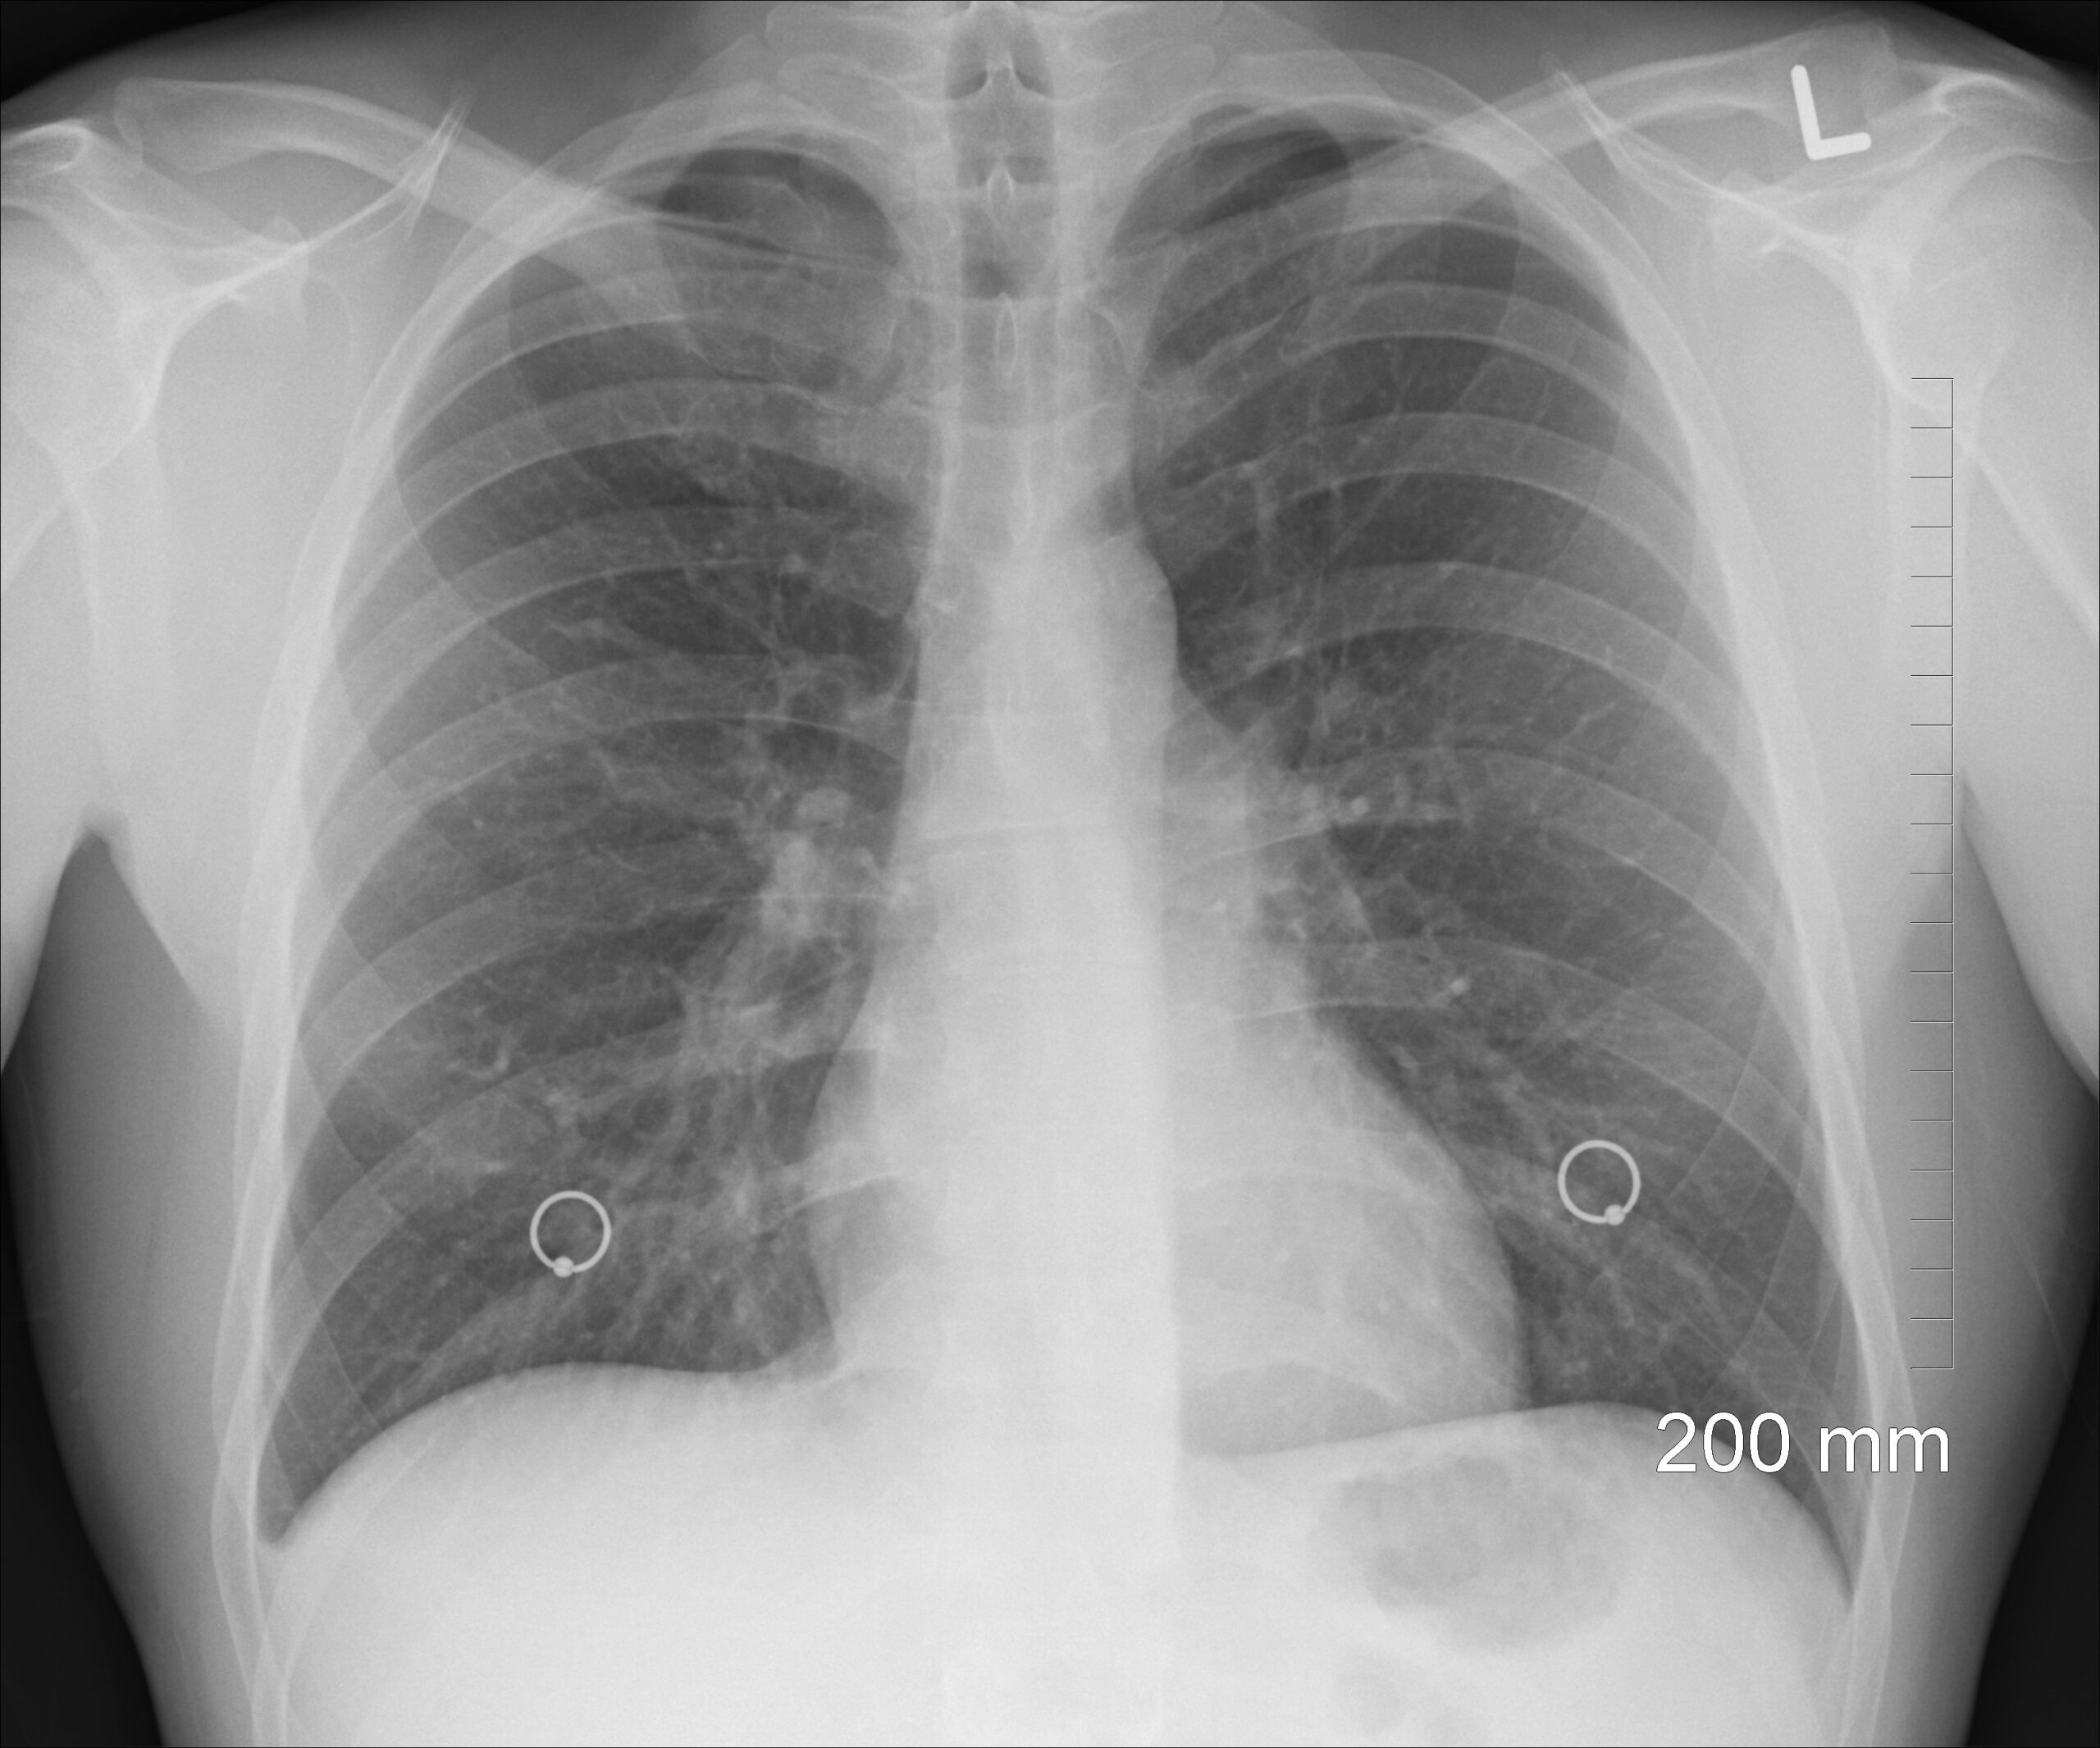

폐암검진 대상자 기준, 흡연 경력이 있다면 꼭 확인하세요

폐암검진 대상자 기준

폐암검진 대상자 기준을 쉽게 정리했습니다. 54세~74세, 30갑년 이상 흡연력, 저선량 흉부 CT 검사와 주기까지 꼭 확인해 보세요. 폐암검진 대상자 기준은 흡연 경력이 있는 중년층이라면 꼭 확인해봐야 하는 내용입니다. 이 글에서는 54세~74세 기준, 30갑년 계산법, 저선량 흉부 CT 검사와 주기까지 쉽게 정리해드립니다. 폐암은 초기에는 특별한 증상이 없는 경우가 많아 검진의 의미가 큰 암입니다. 어느 정도 진행한 … 더 읽기